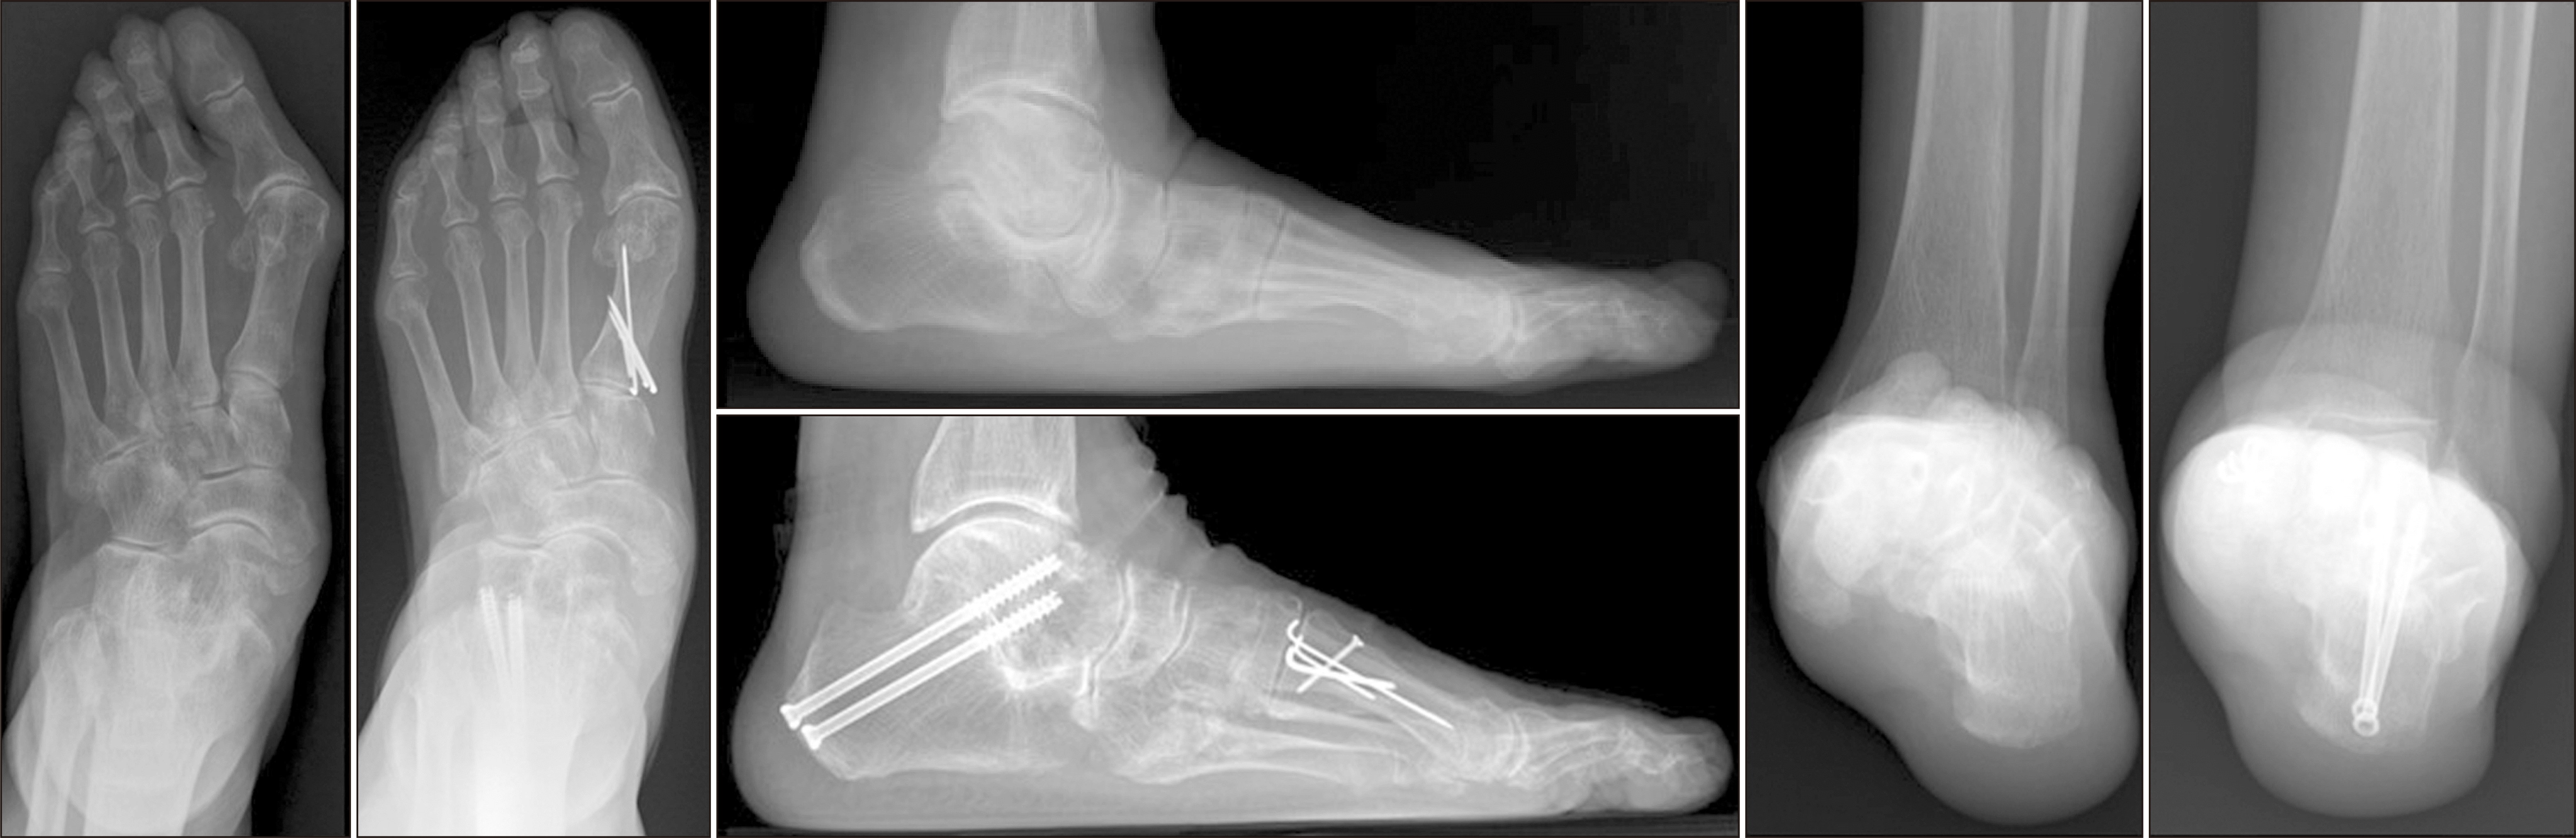

후족부의 관절은 유합할수록 발의 경직성이 심해지는데, 이러한 현상은 특히 거주상 관절에서 도드라진다. Astion 등75)이 시행한 카데바 연구에 따르면 거주상 관절 유합 시 거골하 관절과 종입방 관절의 운동범위가 유합 전에 비해 2%로 감소한 결과를 보였다. 이처럼 Chopart 관절의 유합, 특히 거주상 관절의 유합은 후족부의 운동범위를 극단적으로 제한하여 인접 관절에 가해지는 부담을 증가시킬 수 있어 결국 발목관절이나 중족부 관절의 퇴행성 변화를 일으킬 수 있다.73,75-77) 이에 따라 가능하다면 유합하는 관절을 줄이려는 시도가 이루어지고 있으며, 특히 거주상 관절의 중요성으로 인해 거골하 관절 단독 유합술이나 주상입방 관절 유합술 등이 제시되고 있다.62,77-82) 여러 연구에서 거골하 관절 유합술 단독으로도 좋은 결과를 보고하였으며, 한 연구에서는 거골하 관절 단독 유합술로도 변형을 잘 교정하여 척행족을 얻을 수 있다면 이중 혹은 삼중 유합술 만큼 좋은 결과를 얻을 수 있다고 주장하였다(Fig. 12).78-82)

Figure 12

Pre- and post-operative plain weight bearing foot anteroposterior, lateral, and hindfoot radiographs of a 74-year-old female patient who was underwent subtalar repositional arthrodesis and first metatarsal plantar closing wedge osteotomy.